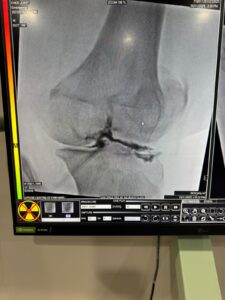

Joint Health: Core Tests, Imaging and Scans

Important tests include:

• Vitamin D levels

• Inflammatory markers (CRP, ESR)

• Thyroid profile

• Rheumatoid factor (if indicated)

• DEXA scan for bone mineral density

The DEXA scan measures bone density.

T-score between -1.0 and -2.5 = Osteopenia

Below -2.5 = Osteoporosis